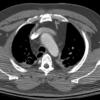

Nl Fat 2b

Date: 04/16/2005

Views: 4977